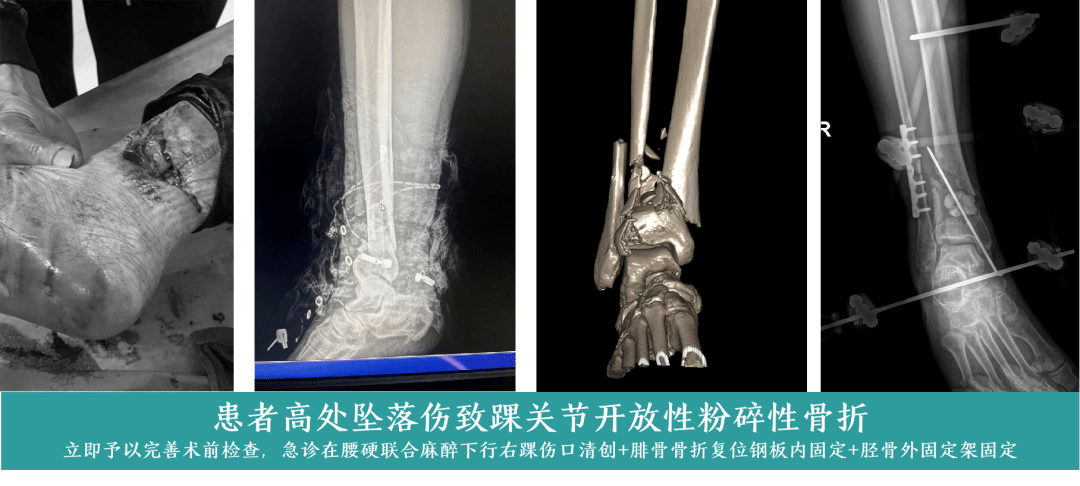

开放性粉碎性骨折